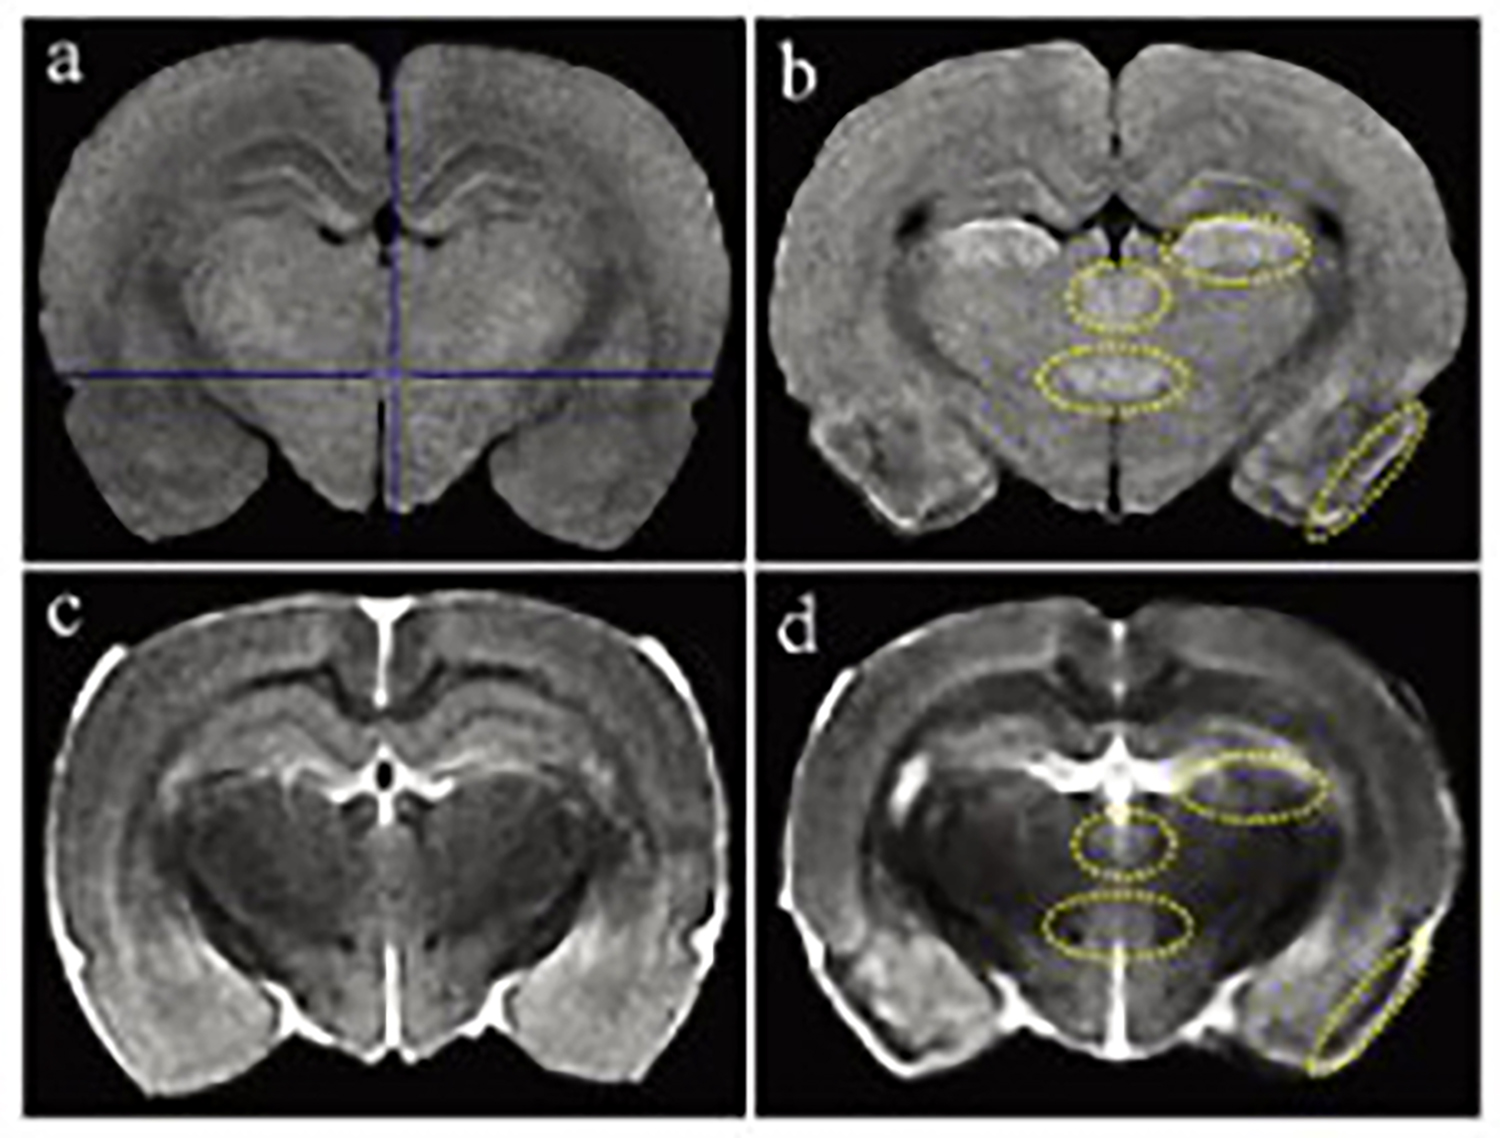

基于MRI(1T)的小鼠生理特征定量计算

磁共振成像(MRI)广泛应用于临床前研究和药物开发,是一种强有力的无创性方法,可用于评估小鼠疾病模型的表型和治疗效果。

小动物磁共振成像(MRI)是一种强大的非侵入性工具,可用于检测临多种病变。